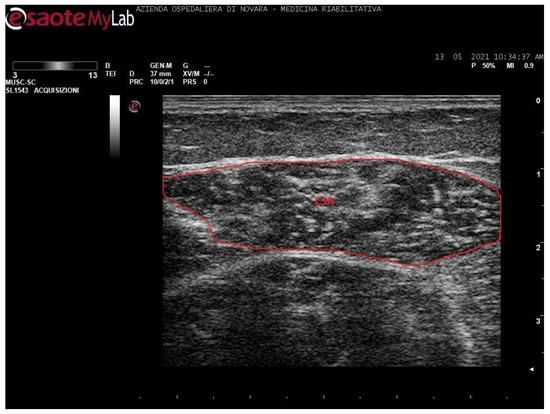

We acquired images of the medial gastrocnemius (MG) and soleus (SOL). Images were processed through the software ImageJ (National Institutes of Health, USA) in order to measure the muscle thickness (MT, cm), the cross-sectional area (CSA, cm2), the pennation angle (α, °), and the mean gray value (MGV, range 0-255). MGV was assessed considering the whole muscle longitudinal section as region of interest (ROI). The gray scale spreads from 0 (black) to 255 (white).

Measurements were taken as shown in Figure 1, Figure 2, Figure 3 and Figure 4.

Notably, soleus CSA presents several technical issues for its measurement. Firstly, in most cases, it is impossible to incorporate the entire area of such a wide muscle in the ultrasonographic frame. Secondly, the deep aponeurosis of SOL does not appear to be uniformly defined in transversal sections of long-standing degenerated spastic muscles, thus preventing an accurate profile definition. For these reasons, the authors preferred not to include such a biased value in this paper. The techinique of SOL CSA measurement was anyway reported in a healthy muscle in Figure 3 for illustrative purposes.

Figure 3. Ultrasound image of soleus in transversal section. In red: cross-sectional area (CSA).